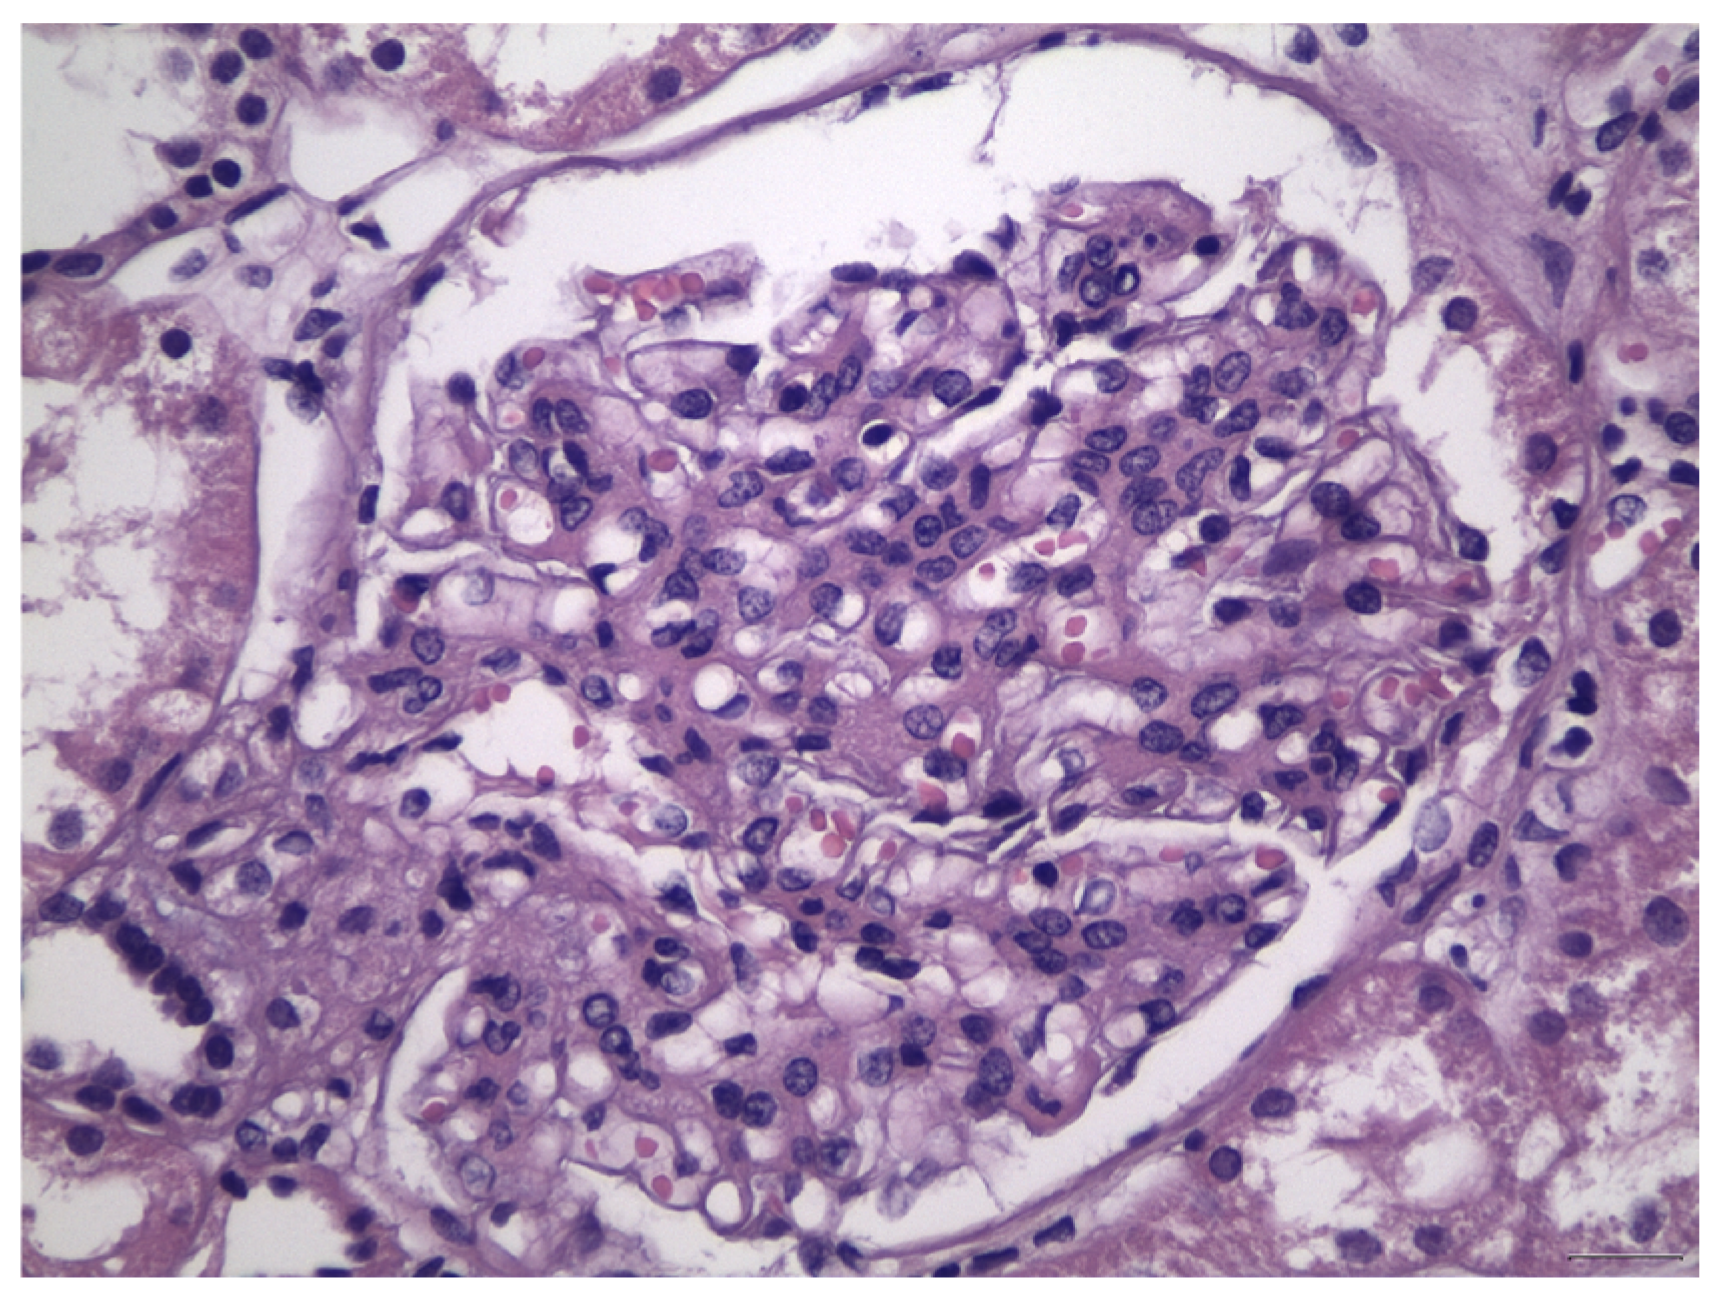

Histologically, IgAN is characterized by increase of the mesangial matrix and mesangial cell proliferation, as well as strong, dominant IgA deposition (≥2+), usually accompanied by C3 complement component, and/or IgG immunoglobulin in a lesser degree than IgA immunoglobulin and l light chain deposition, in Immunofluorescence examination. Although many cases show only mesangial proliferation, there are some cases that exhibited both mesangial and endocapillary proliferation with the influx of inflammatory cells into capillary lumens, or even extra-capillary proliferation, with glomerular crescents formation. Segmental glomerular sclerosis/scarring is also another relatively common feature, mimicking sometimes, focal segmental glomerulosclerosis, in cases showing signs of chronicity. Mesangial electron-dense deposits and a few small scattered subendothelial deposits are typically found in Electron Microscopy (EM) examination, although, in some cases, subendothelial deposits can be large. Rarely, a few small subepithelial deposits can also be recognized, although with no true membranous pattern. The tubulointerstitial department may show varying degrees of interstitial fibrosis or tubular atrophy, as well as red blood cell casts into tubular lumens. Thus, IgA nephropathy exhibits a wide spectrum of histological variability, ranging from no essential histological abnormalities to diffuse proliferative and crescentic glomerulonephritis, although most common histological patterns include focal or diffuse mesangial proliferative glomerulonephritis. Without treatment, some of the cases will progress to interstitial fibrosis and tubular atrophy, as well as glomerular scarring and loss, leading to end-stage renal disease. Taking into account the high histological diversity of the disease, but also clinical course variability, several histological grading schemes have been developed and proposed after Berger’s original disease description [12], in order to optimize therapeutic intervention and even to predict patients’ clinical course, among them, the Haas grade scheme is one of the most widely used [13]. The Oxford Classification grading scheme gained interest in the recent years and after Consensus meetings, the MEST-C score is highly recommended to be applied in every case [14,15]. In MEST-C (from Heptinstall’s Pathology of the kidney [16]), M0 or M1 indicate mesangial hypercellularity (≥4 cells in one or more mesangial areas) in ≤50% vs. >50% of glomeruli. E0 or E1 indicate endocapillary hypercellularity in zero vs. one or more glomeruli. S0 or S1 indicate segmental sclerosis in zero vs. one or more glomeruli. T0, T1, or T2 indicate tubular atrophy/interstitial fibrosis in ≤25%, 26% to 50%, or 50% of the renal cortex, respectively. C0 or C1 or C2, if cellular and/or fibrocellular crescents are absent, present in at least one glomerulus or at least 25 percent of glomeruli. Fibrous crescents are not counted toward this score (Figure 1, Figure 2, Figure 3 and Figure 4).

Figure 2.

Severe increase in mesangial matrix and mesangial cell proliferation, in association with foci of endocapillary proliferation, in the case of IgA nephropathy, class M1E1S1T1, according to Oxford Classification.